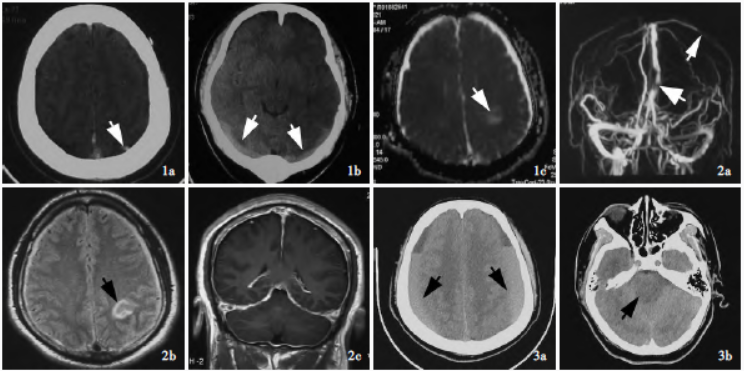

图1 溶栓治疗前后影像学检查所见,1a 溶栓前(2021年9月5日)横断面CT显示左侧顶叶皮质静脉及上矢状窦高密度影(箭头所示),考虑血栓形成,1b 溶栓第2天(2021年9月6日)横断面CT可见双侧横窦增宽,呈条状高密度影(箭头所示) ,1c 溶栓治疗第2 天(2021 年9 月6 日)横断面ADC 图显示左侧顶叶混杂高低信号影(箭头所示),提示静脉性梗死;图2 溶栓治疗第7 天(2021年9月14日)MRV和MRI检查所见,2a 增强MRV显示,上矢状窦中下段局限性显影欠佳(粗箭头所示),左大脑上静脉局部显影欠佳(细箭头所示) ,2b 横断面FLAIR 成像显示,双侧硬膜下血肿,左侧顶叶局部脑组织肿胀伴不均匀高信号影(箭头所示),考虑静脉性梗死伴出血,2c 冠状位增强T1WI显示,硬脑膜弥漫性增厚伴强化改变;图3 2021年10月11日入院时横断面CT检查所见,3a 双侧额顶叶硬膜下积血伴液-液平面(箭头所示) ,3b 脑干腹侧受压,第四脑室消失(箭头所示)

溶栓第2天复查CT显示双侧横窦增宽,呈条状高密度影(图1b);MRI 提示左侧顶叶静脉性梗死(图1c)。溶栓第7 天头痛突然加剧,表现为全头部持续性胀痛,头部MRV 检查上矢状窦后1/3 及左大脑上静脉显影欠佳,拟诊脑静脉系统血栓形成(图2a),予脱水降低颅内压、抗凝治疗,甘露醇

(3.75 mg/d)口服;复查MRI 显示双侧硬膜下血肿、左侧额顶叶静脉性梗死伴出血,增强扫描呈弥漫性硬脑膜强化征象(图2b,2c),未予处理。

患者共住院23天,出院时临床症状好转,遵医嘱继续服用华法林,剂量同前。7天前晨起头痛症状突然加重,出现非喷射状呕吐,社区医院静脉滴注甘露醇(125 ml/8 h),3 天后逐渐出现意识障碍,呼之可睁眼,遂急诊转入我院,头部CT显示双侧额颞顶叶硬膜下血肿伴积液,脑室和脑干明显受压、移位(图3)。急诊以脑静脉系统血栓形成、左侧顶叶静脉性梗死、双侧额颞顶叶硬膜下血肿,以及自发性低颅压综合征待查收入院。患者既往高血压病史2 年,血压最高达140/110 mm Hg(1 mm Hg = 0.133 kPa),规律服用厄贝沙坦氢氯噻嗪